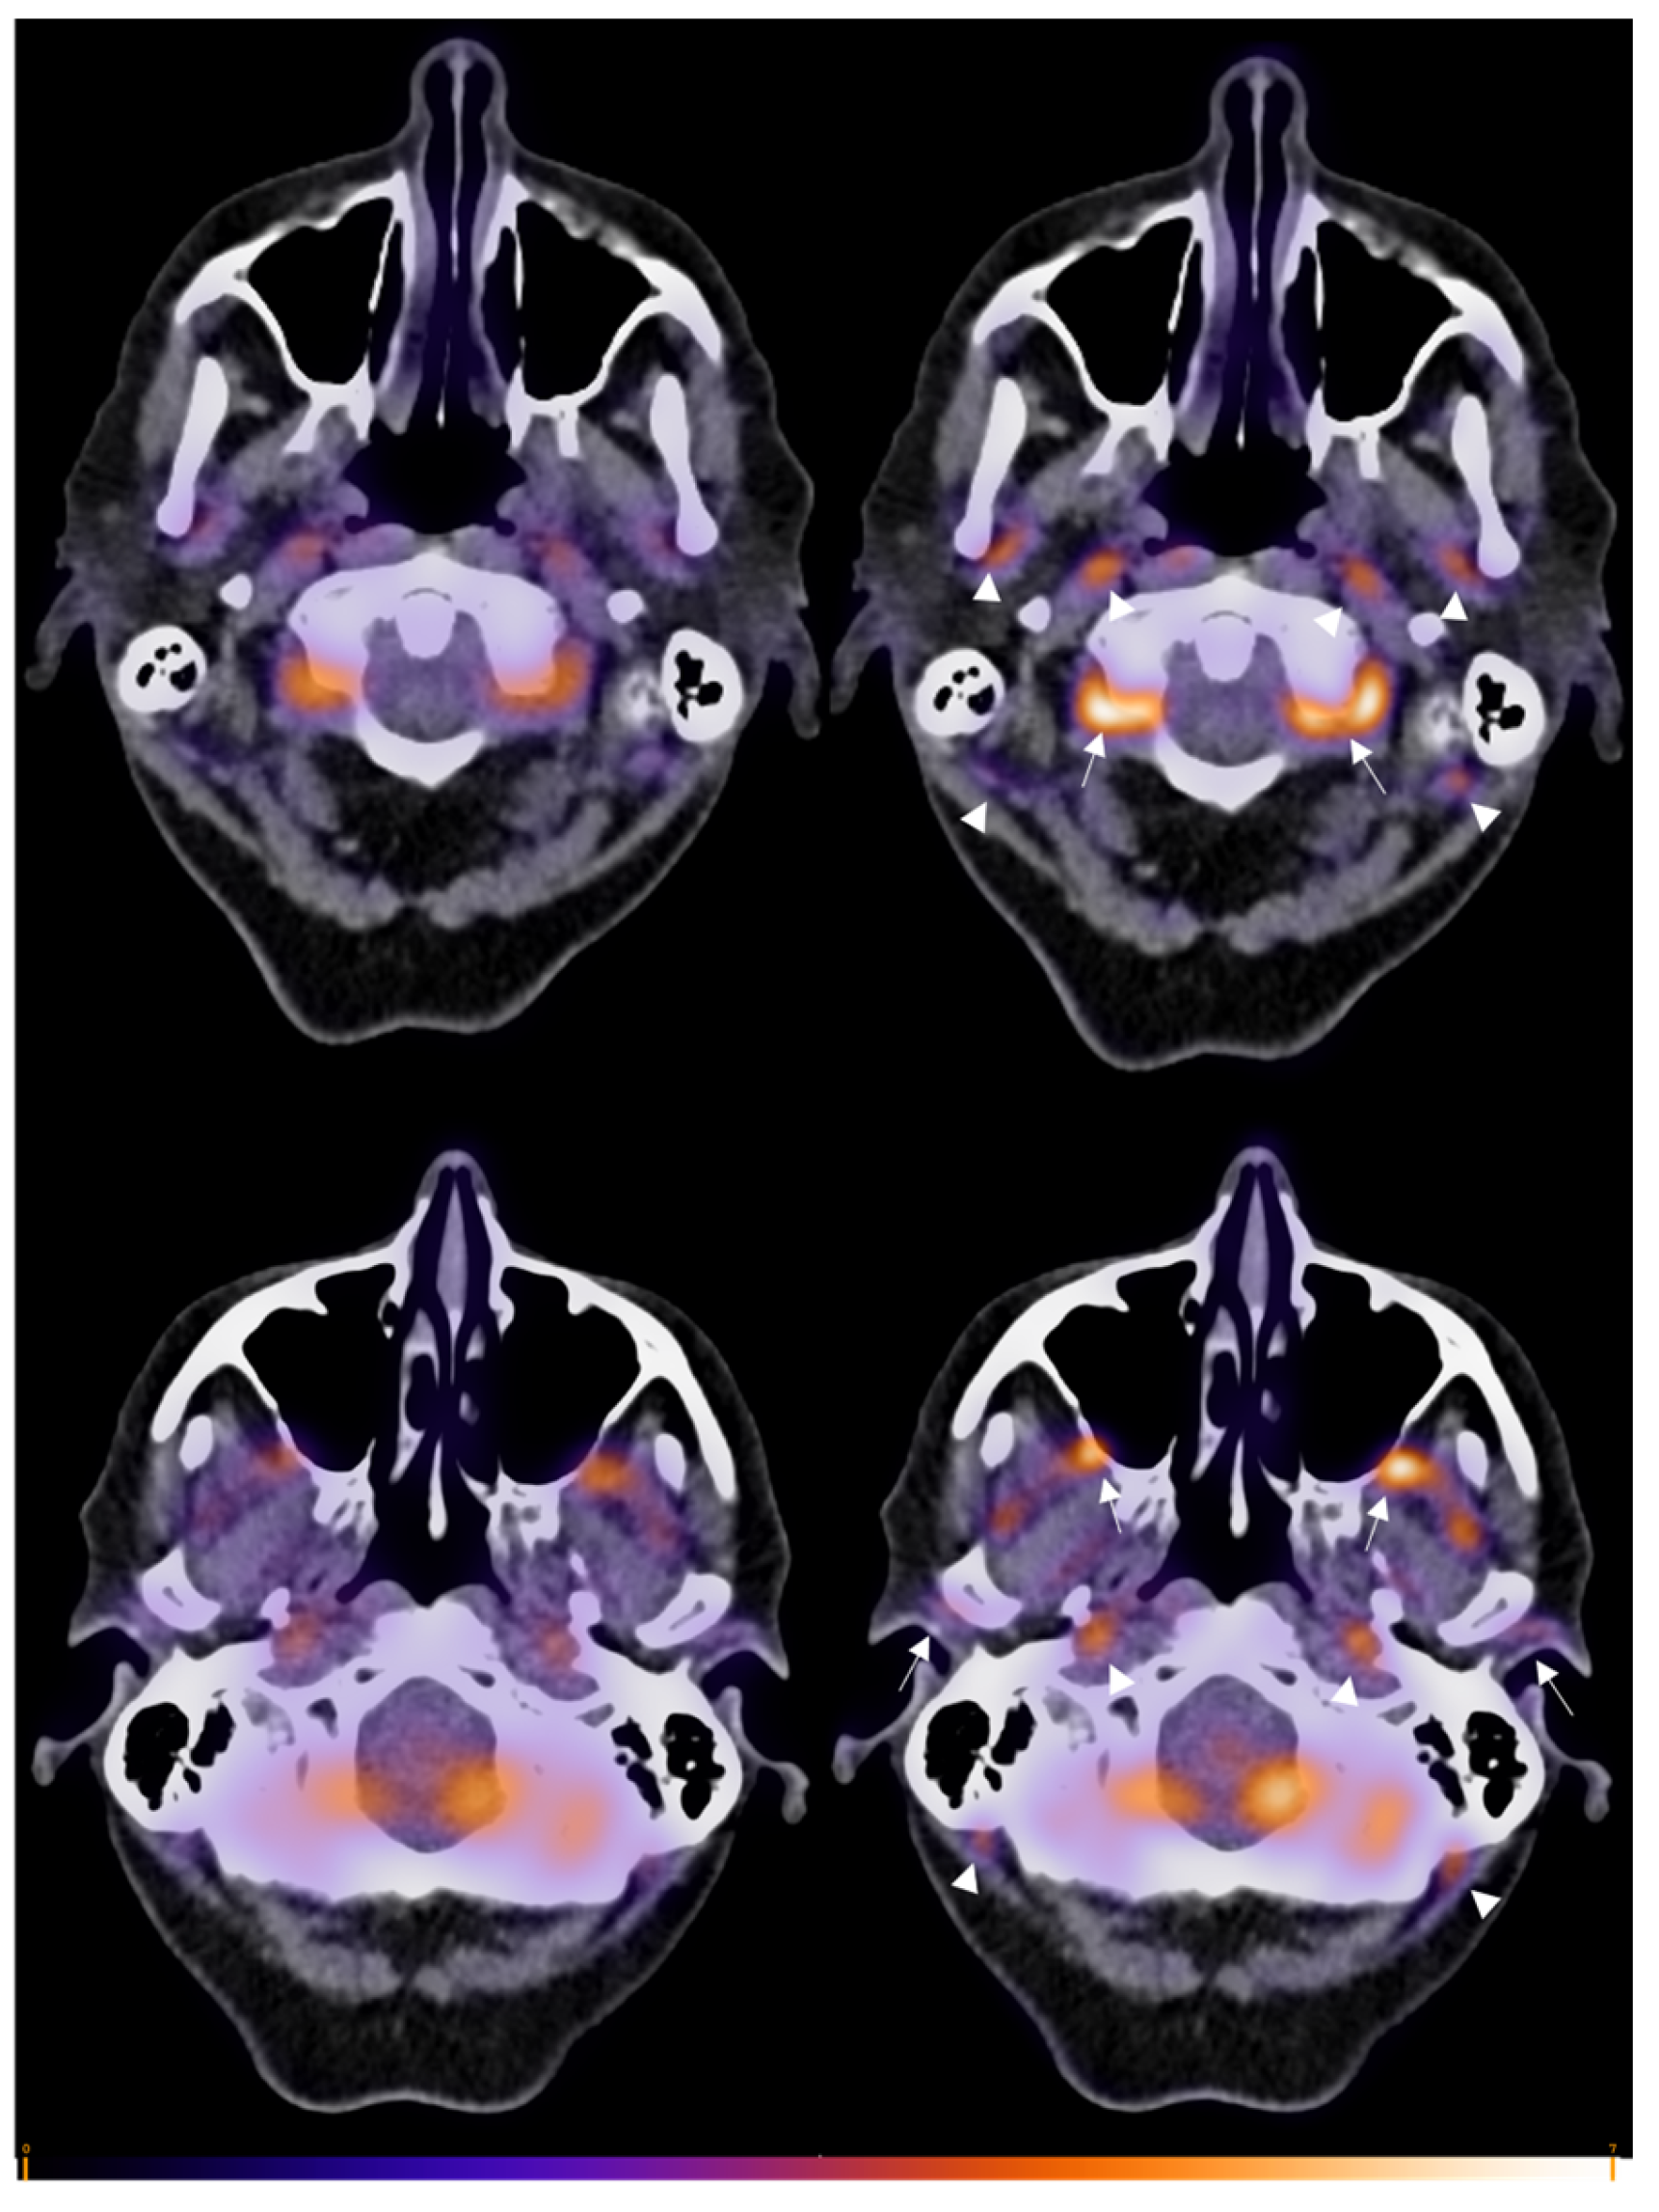

2.2. Imaging and Assessment